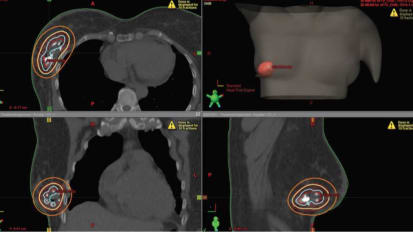

Clinical Minutes: Microsurgical and Radiosurgical Treatment of Metastatic Tumors

George J. Counelis, MD, Medical Director of the Brain Tumor & Neuro-Oncology Program, discusses the technology available within the department's Radiosurgery program - allowing precise treatment for cancer patients.

Stereotactic Radiosurgery (SRS) at John Muir Health TRUE Radiosurgery

This white paper explores the treatment of brain and spinal cord cancer which is dependent on the on the tumor’s size, location, and type, as well as the patient’s age and general health.

Stereotactic Radiosurgery at John Muir Health

A collaboration of the JMH Neuroscience Institute and JMH Cancer Institute Providing “best in class” treatment and care.